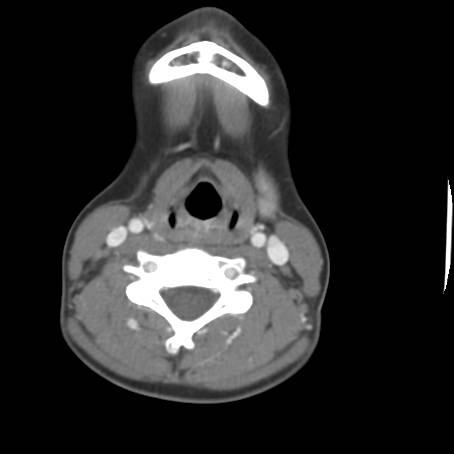

![]() Figure 5b |

Describe CT.